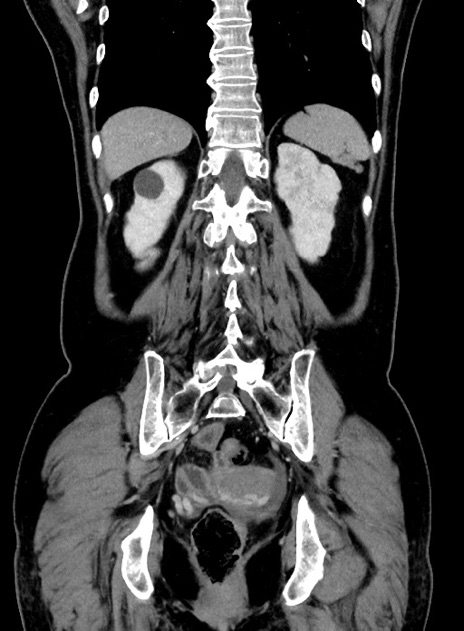

症例9(冠状断像)

【症例】 60歳代女性

【主訴】むかつき、みぞおちの痛み

【現病歴】3日前よりむかつきがあり、食事がとれない。

【既往歴】糖尿病

【身体所見】発熱なし、心窩部圧痛軽度あるも、腹膜刺激症状なし。

【データ】WBC 7400、CRP 1.92